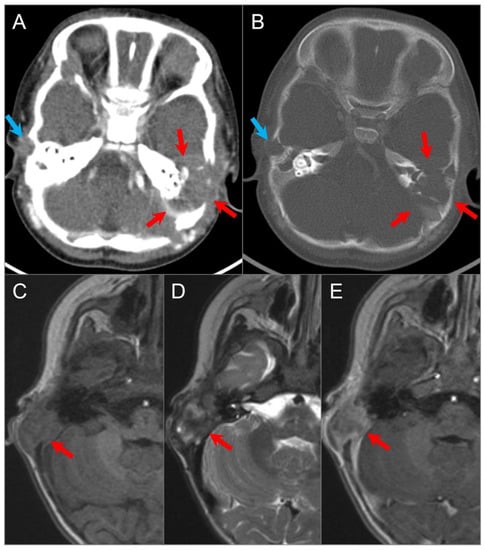

4.4.1. Chordoma

4.4.2. Chondrosarcoma